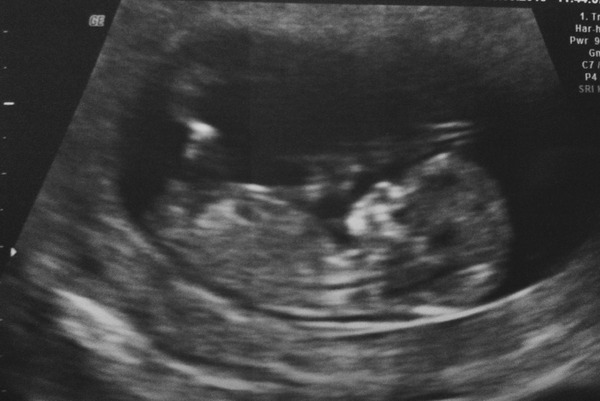

MazzleDazzle · 26/09/2015 12:31

Yay! Scan went well and they've moved me forwards. I'm now 12+1. Grin

Also had my 12 week scan this week and they have moved me forward so I'm, 13+1 today! Congratulations to everyone having scans, some lovely pictures on the thread!

Love seeing all the lovely scans... Has anyone done any nub theories? I've posted elsewhere and all whom commented said girl! I have no idea what to even look at ha ha... hope ur all well xx

Lovely pic Mazzle!

I had to look up what all this nub talk was about.

Looking at the scan I'm thinking a boy but I've just got a gut feeling it's another boy anyway going by how different my pregnancies with DD and DS where, and I've said he or him a few times without thinking.